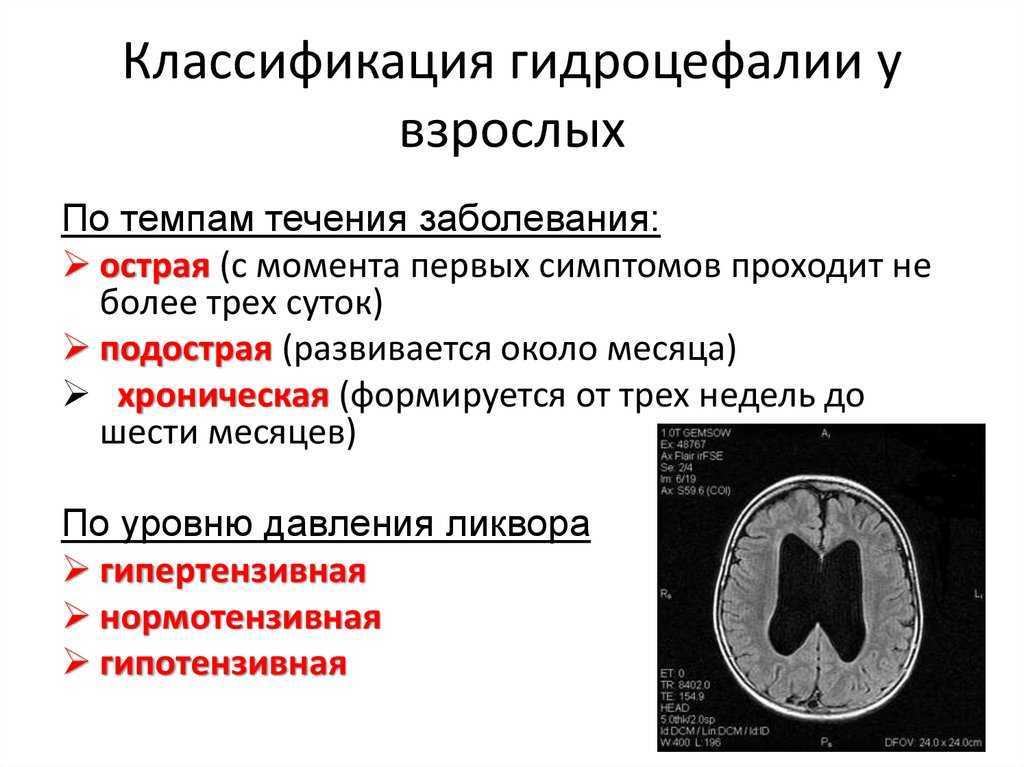

Признаки умеренно выраженной наружная

Признаки умеренно выраженной наружная 113 фото